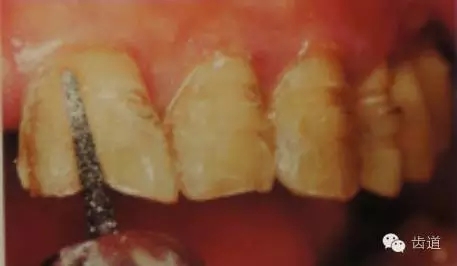

5、齦緣制備:通常瓷貼面的齦端邊緣位于齦上近齦緣處,但當美觀要求時也可以設計在齦下0.5mm。

預備齦下邊緣之前要先排齦,之后選用圓頭錐形車針磨除牙體到所設計的邊緣位置。

1)排齦

2)制備